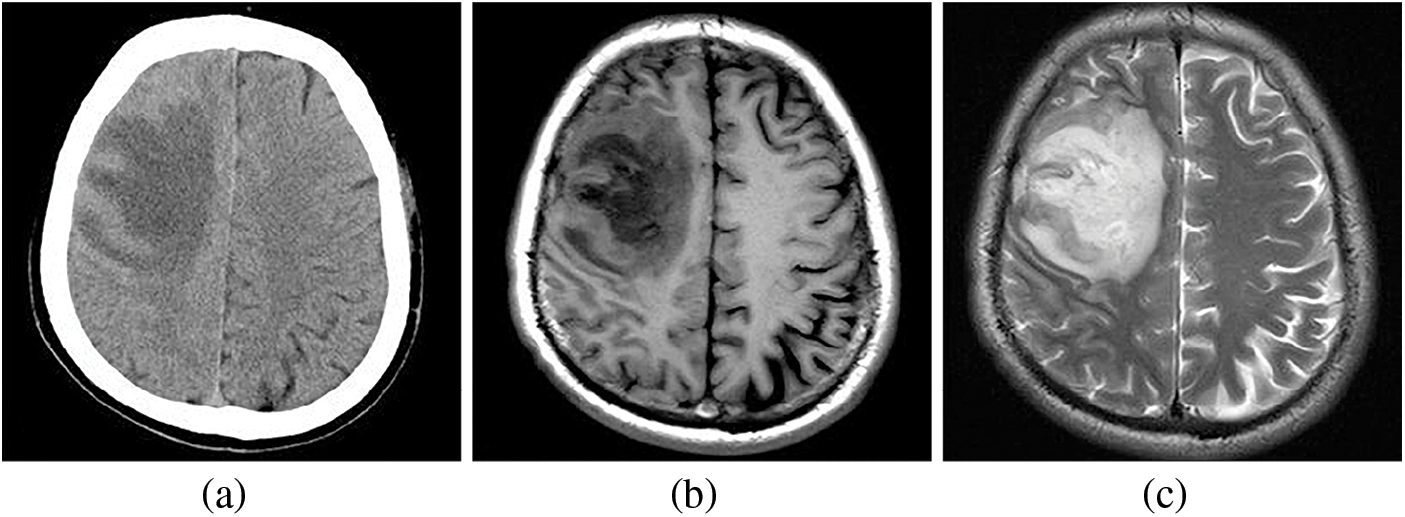

While various techniques are employed for imaging the brain, magnetic resonance imaging (MRI) is a more robust and effective option than computed tomography (CT). Although brain CT scans may offer superior contrast, they often suffer from noise, limiting the radiologist’s ability to assess medical images thoroughly [9]. Fig. 1 visually compares CT and MRI brain images [10,11]. Notably, CT images of the brain reveal hypodensity in the right frontal lobe. In contrast, T1 and T2 weighted MRI scans also show lesion hypointensity but with reduced noise, providing a superior representation. Brain tumors present diverse classifications based on behavior and therapeutic considerations, and effective management helps minimize the need for biopsies by accurately categorizing them as benign or malignant [12,13].

Figure 1: Comparing the CT and MRI images of the brain, (a) displays hypodensity in the right frontal lobe on the brain CT images. Additionally, (b) and (c), representing T1 and T2 weighted MRI images, respectively, reveal hypointensity in the lesion with reduced noise, providing a clearer and more accurate image representation